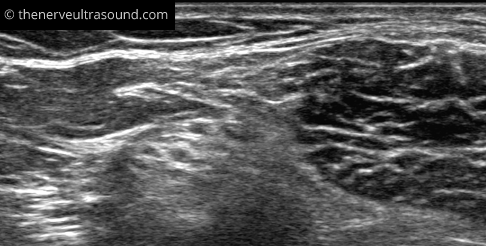

Primary palpation of the groove between the semitendinous and the long head of the biceps femoris muscle makes it easier to find the sciatic nerve in the subgluteal region. Here, the fascia between the two muscles often has an S-shaped aspect pointing to the sciatic nerve deep to the muscles.

The sciatic nerve lies quite superficial at the subgluteal region and the popliteal fossa. In between the nerve runs deeper and might be difficult to identify clearly in obese patients. Starting the scanning more distally at the position E in the knee fold makes it easier to identify the nerve at the positions C and D.